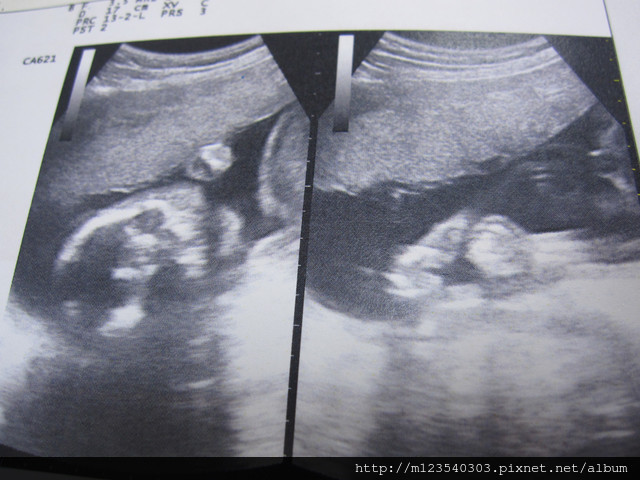

此外~還是要來看看小寶貝的狀況

這是握拳頭的小手手

一邊是小腳腳

另一邊就可以看得出性別了~是妹妹喔!!

醫生說:小寶貝的狀況不錯大小也剛剛好....所以...都胖在媽媽身上ㄟ....